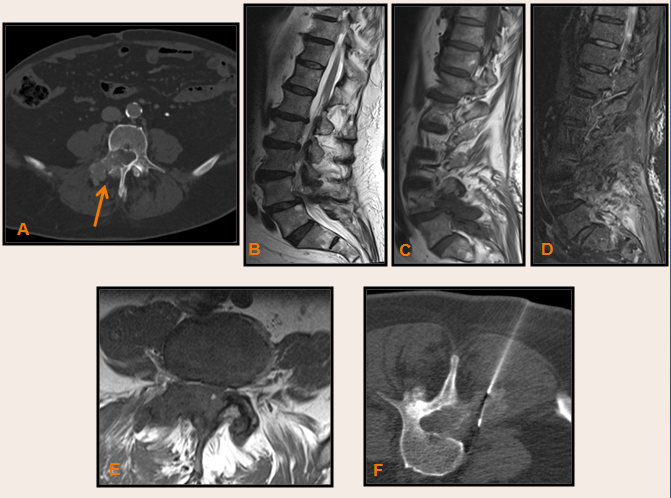

A. Imagen axial de TC abdominal con ventana de hueso dónde se observa lesión lítica polilobulada en elementos posteriores derechos de L4 con extensión intraraquídia a este nivel; sin otros hallazgos de interés.

B. Secuencia T2 sagital de RM lumbar que demuestra lumbodiscartrosis difusa y lesiones focales en L4 y L5.

C. Secuencia T1 sagital de RM lumbar dónde se observan lesiones hipointensas en lámina y articulación interapofisaria derecha de L4 y también, aunque en menor grado, en L5.

D. Secuencia STIR sagital de RM lumbar dónde las lesiones en L4 y L5 muestran hiperseñal franca.

E. Secuencia T1 axial de RM lumbar centrada en L4 con hallazgos superponibles a la TC abdominal.

F. Se realizó biopsia percutanea de la lesión derecha de elementos posteriores de L4 con trucut del 19G guiada por TC fluoroscopia.